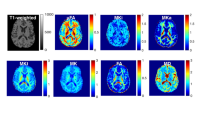

Distinctive cerebral lesions with disruptions to the developing white matter are found in very low birth weight (VLBW) infants. Although hypoxia-ischemia (HI) is a causal pathway, the pathogenesis of cerebral white matter injury in the VLBW infant is not fully understood. Pertinent murine models would facilitate the investigation of the processes leading to these cerebral lesions and enable the evaluation of therapeutic strategies. Postnatal d 3 (P3) rats are at a stage of cortical oligodendroglial maturation and axonal outgrowth similar to very preterm infants. Our aim was to characterize the effects of a focal hypoxic-ischemic injury at P3 on subsequent cerebral development. Three groups of P3 Wistar rats were investigated: group I underwent right carotid ligation followed by 6% hypoxia for 30 min (HI), group 2 had carotid ligation only, and group 3 had no intervention. At P21, in the HI group, the right cortical area was reduced compared with controls (p < 0.01). There were no significant alterations in the size of the dorsal hippocampus, striatum, and thalamus. The cortical myelinated area was reduced in the HI animals compared with controls (p < 0.01). There was a corresponding loss of myelinated axons extending up into the cortex, with deep cortical neuronal and axonal architecture markedly disrupted. Glial fibrillary acidic protein immunohistology showed a reactive gliosis in the deep parietal cortex (p < 0.01). Moderate HI injury in the immature rat brain compromised cortical growth and led to a selective alteration of cortical myelinated axons with persistent gliosis. These alterations induced at P3 by unilateral HI share neuropathological similarities with the diffuse white matter lesions found in VLBW infants.